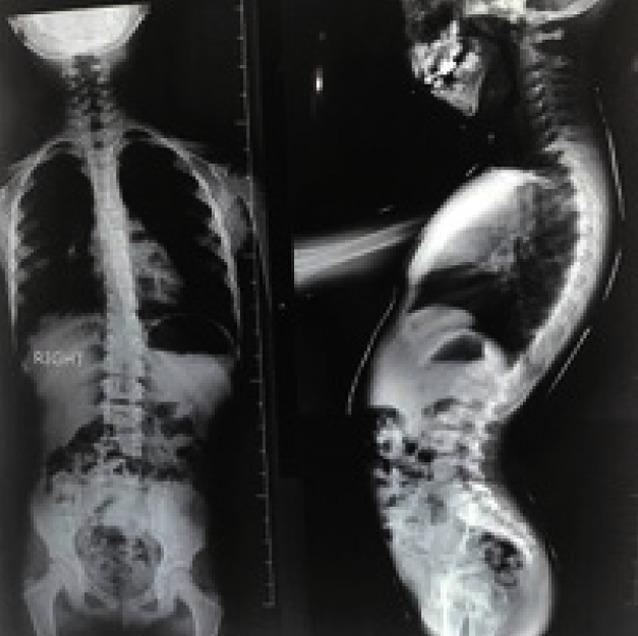

Goldenhar syndrome (GHS) is a complex syndrome characterized by relation of mandibular hypoplasia, abnormality of the ear, ocular dermoid and vertebral disorders and hemi facial macrosomia. Treatment protocol depends on the patient's age and systemic clinical presentations, with a multidisciplinary method often being required. This case report describes a typical 6-year-old female patient who presented to the Department of Pediatric Dentistry, Faculty of Dentistry, University of Medical Sciences, Kerman, Iran with mandibular hypoplasia, facial asymmetry, ear tags and ocular dermoid after plastic surgery. Diagnosis was based on clinical aspects, radiology and laboratory findings. GHS is a developmental complaint that can disturb many aspects of the patient's life; therefore, immediate treatment from birth is necessary.

戈尔登哈综合征(GHS)是一种复杂的综合征,其特征为下颌发育不全、耳部异常、眼皮样囊肿、脊柱疾病以及半侧颜面巨大症。治疗方案取决于患者的年龄和全身临床表现,通常需要多学科方法。本病例报告描述了一名典型的6岁女性患者,她因下颌发育不全、面部不对称、耳赘和眼皮样囊肿在接受整形手术后就诊于伊朗克尔曼医科大学牙科学院儿童牙科。诊断基于临床症状、放射学和实验室检查结果。戈尔登哈综合征是一种发育性疾病,会干扰患者生活的许多方面;因此,从出生起就需要立即进行治疗。